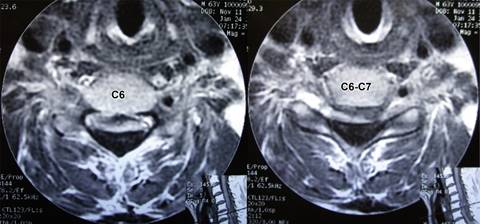

A la exploración inicial: paciente en silla de ruedas, con ausencia de equilibrio de tronco, frecuencia cardiaca de 80 l/min; frecuencia respiratoria de 16 r/min; tensión arterial de 110/60 mmHg, cráneo, cara y cuello al igual que pares craneales normales; tórax con ampliación y amplexación disminuidas, murmullo vesicular normal, ruidos cardiacos rítmicos sin fenómenos agregados; sensibilidad normal a nivel de C4 con hipoestesia profunda por abajo de horquilla esternal; abdomen, blando depresible, sin visceromegalias; reflejos cutáneo abdominales aumentados; miembros superiores con arcos de movimiento pasivos completos; examen clínico muscular para miembro superior derecho con calificación 0/5 de deltoides hacia abajo, miembro superior izquierdo deltoides en 4/5, bíceps braquial, coracobraquial y braquial anterior en 3/5, resto de musculatura en 0/5, por lo que se diagnostica lesión de neurona motora inferior en C5 derecha y C6 izquierda. Reflejos osteotendinosos tricipital, bicipital y estiloradial +++ bilateral; Hoffman bilateral presente; genitales normales, ausencia de reflejo anal; extremidades pélvicas: contractura en flexión de caderas, rodillas y tobillos por espasticidad, hipotrofia muscular generalizada de miembros pélvicos, examen clínico muscular en 0/5 bilateral; reflejos osteotendinosos rotulianos y aquileos +++, sensibilidad ausente. Babinski presente bilateral, conformando una lesión de neurona superior a nivel C6 derecha y C7 izquierda; siendo clasificada como grado V en la escala de Nurick. Se solicitó resonancia magnética mostrando: canal estrecho por presencia de ligamento amarillo hipertrófico de C2 a C7 (Figuras 1 a 3). Considerando tanto al área medular como a la del canal espinal como elipses, se utilizó fórmula para su cálculo (A = π × R1 × R2), así como al índice de Torg-Pavlov para valorar sus relaciones (Tabla 1). Con diagnóstico de mielopatía con nivel motor en C5, C6 y nivel sensitivo C5 derecha y C6 izquierda. Se interviene quirúrgicamente practicando laminectomía de las vértebras C3, C4, C5, C6 y C7 encontrando ligamento amarillo hipertrófico, el cual se reseca en su totalidad de C3 a C7, quedando el saco dural libre y latiendo, cerrando por planos. El estudio de patología reportó: cortes histológicos mostrando múltiples fragmentos de ligamento amarillo con mineralización y pérdida de la periodicidad de las fibras y cambios degenerativos moderados.

Figura 3: Imágenes de resonancia magnética ponderadas en T2, a nivel C6 y espacio C6-C7, mostrando dimensiones del canal espinal estrecho por hipertrofia del ligamento amarillo que ocasionó mielopatía (cuadriplejía) en femenino de 63 años.